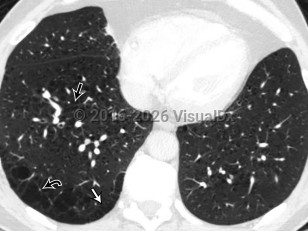

Acute respiratory distress syndromeAcute respiratory distress syndrome

Acute eosinophilic pneumoniaAcute eosinophilic pneumonia